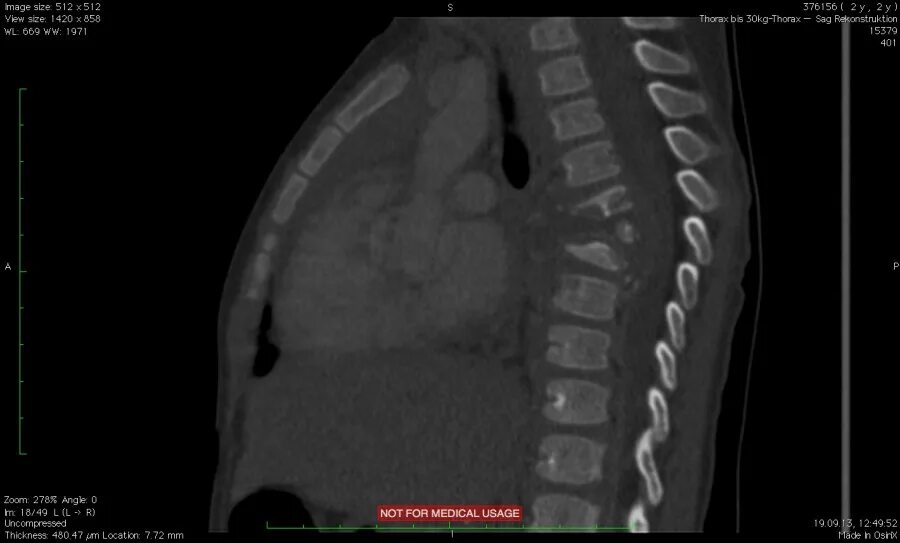

Спондилодисцит мкб